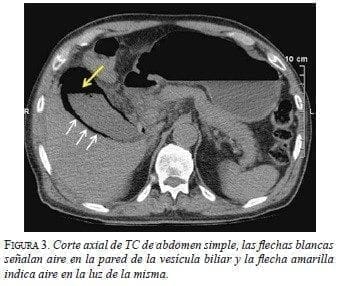

La radiografía simple de abdomen sugirió infiltración de aire perivesicular. Se complementó con TC de abdomen y se confirmó una colecistitis enfisematosa sin neumoperitoneo (figuras 1-3).

![]() |

Se inició manejo antibiótico con ciprofloxacina y metronidazol. Posteriormente, se practicó colecistectomía abierta (según criterio del cirujano dada la complejidad de los hallazgos), en la cual se evidenció aire en la pared de la vesícula biliar y se drenaron 80 ml de líquido hemato-purulento perivesicular.